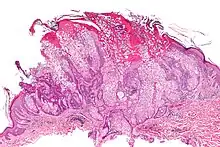

| Micrograph of a sebaceous adenoma, as may be seen in Muir–Torre syndrome. H&E stain. | |